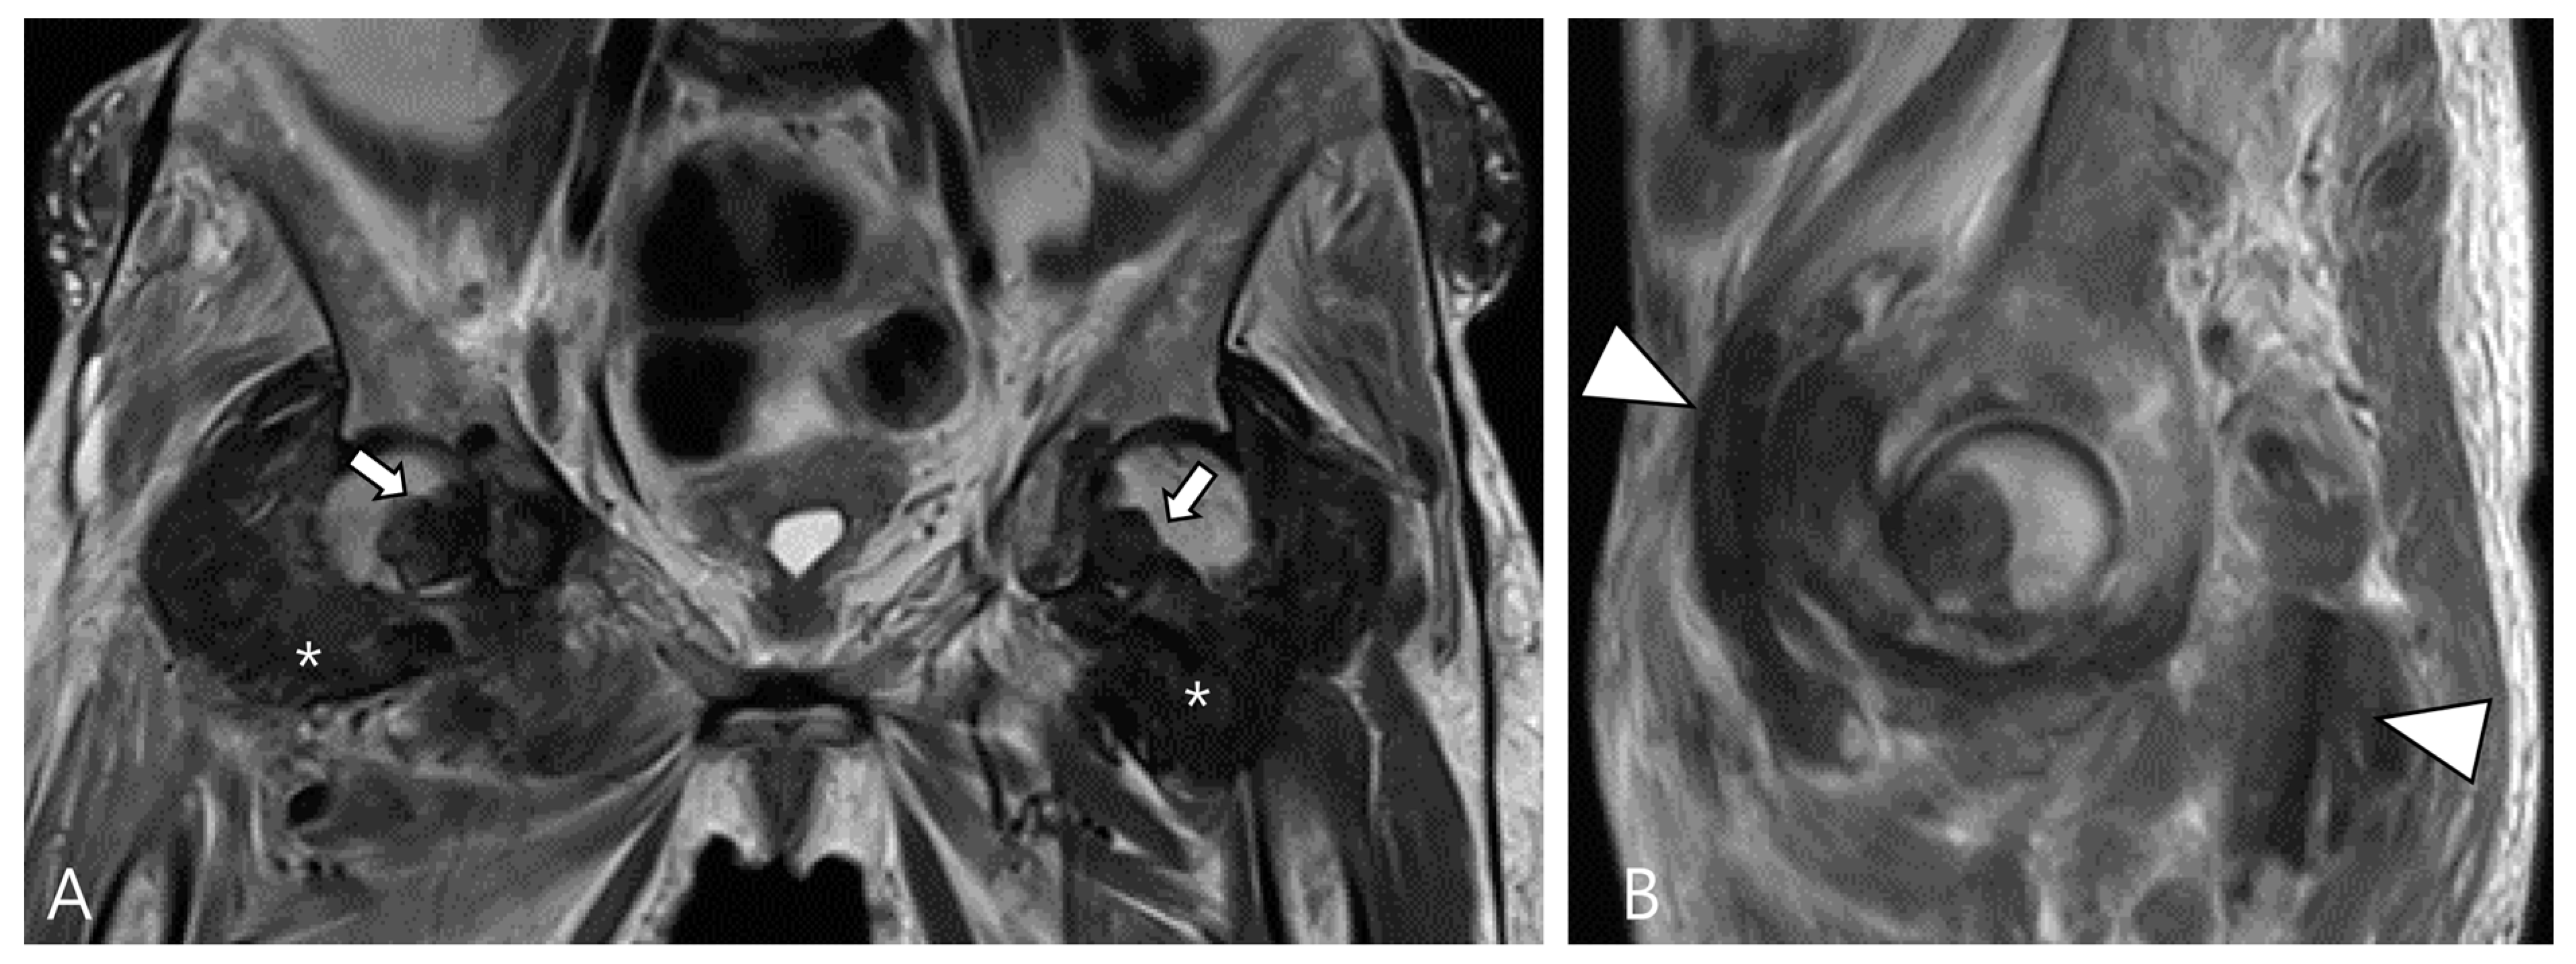

3.1.2. Synovial Chondromatosis

- Murphey, M.D.; Vidal, J.A.; Fanburg-Smith, J.C.; Gajewski, D.A. Imaging of synovial chondromatosis with radiologic-pathologic correlation. Radiographics 2007, 27, 1465–1488. [Google Scholar] [CrossRef] [PubMed]